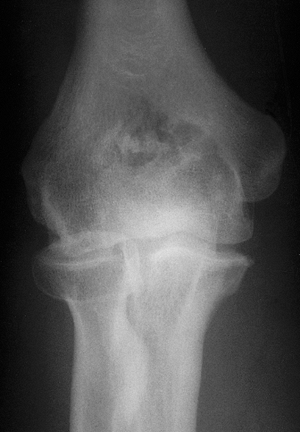

![]() |

|

Figure 20-18. The olecranon and coronoid foramen are ossified on the anteroposterior view.